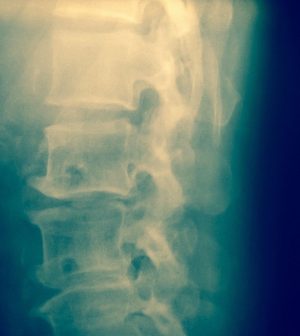

Brain Wave Decoder Figures Out How To Cause Movement In Spinal Cord Injuries

A brain wave decoder shows promise in using electrical stimulation to the spine to cue leg movement, researchers say.

The decoder could one day help restore mobility in people with spinal cord injuries.

Tests in 17 people without a spinal cord injury showed that the decoder could cue movement in their lower legs using spinal cord stimulation, researchers reported in the Journal of NeuroEngineering and Rehabilitation.

Using those brain waves, people were able to move their lower leg by just thinking about it, with an external electrode stimulating their spinal cord into producing the movement, researchers reported.

The study is a first step toward developing a brain-spine interface that uses real-time brain waves and spinal cord stimulation to promote movement in people with a spinal cord injury, researchers said.